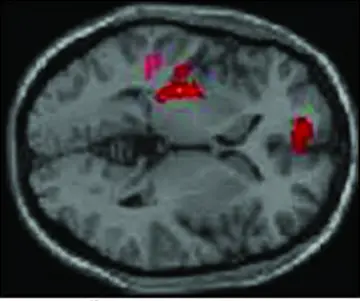

فعال‌شدن نورون وآکوپونکتور

شماره ۱۰۱۶